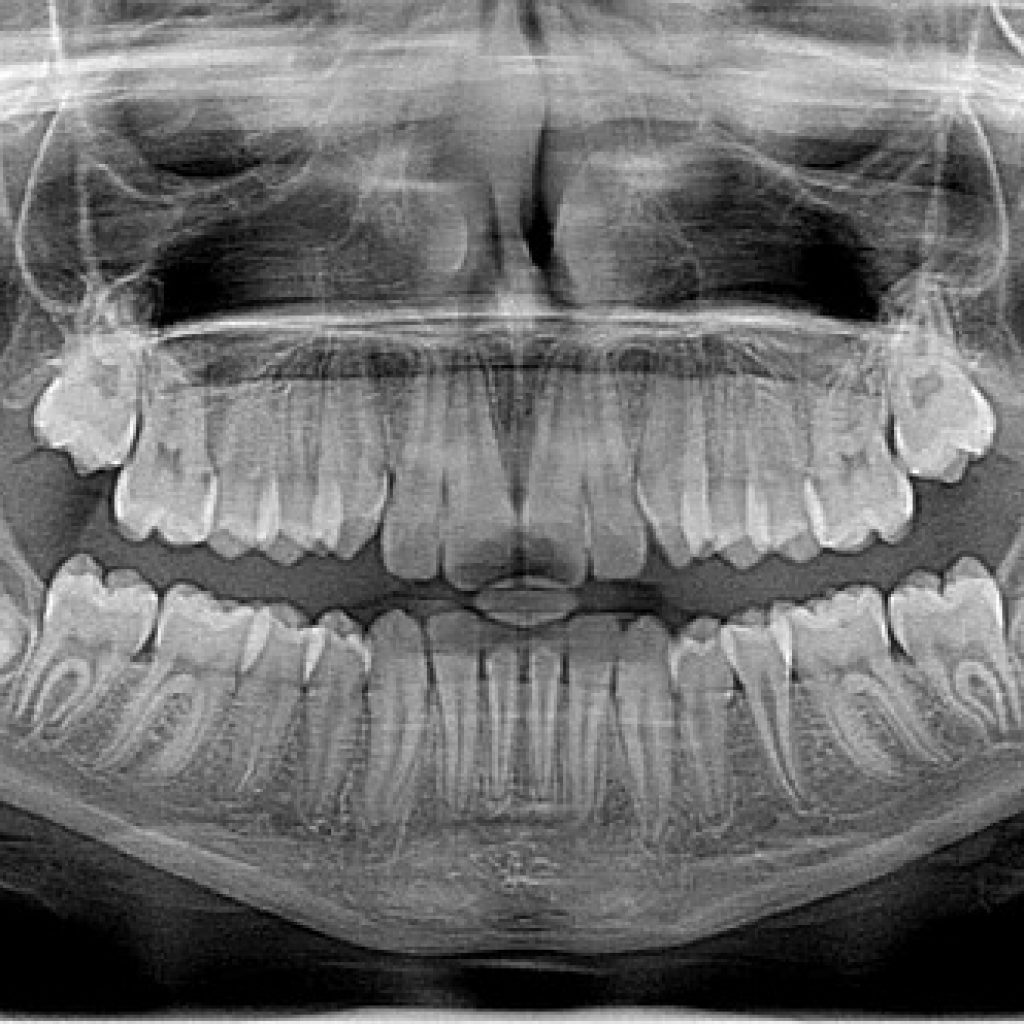

When a person has a cavity, they often have it filled in order to prevent the decay from spreading. However, if that filling is not properly sealed, it can lead to a cracked cavity. This is a condition where the tooth material around the filling is eroded, which can cause significant pain and sensitivity. If left untreated, a cracked cavity can lead to further tooth decay and even loss of the tooth. Diagnosis of a cracked cavity is made through a visual examination and X-rays. Treatment typically involves re-filling the cavity and using a sealant to prevent future cracking.